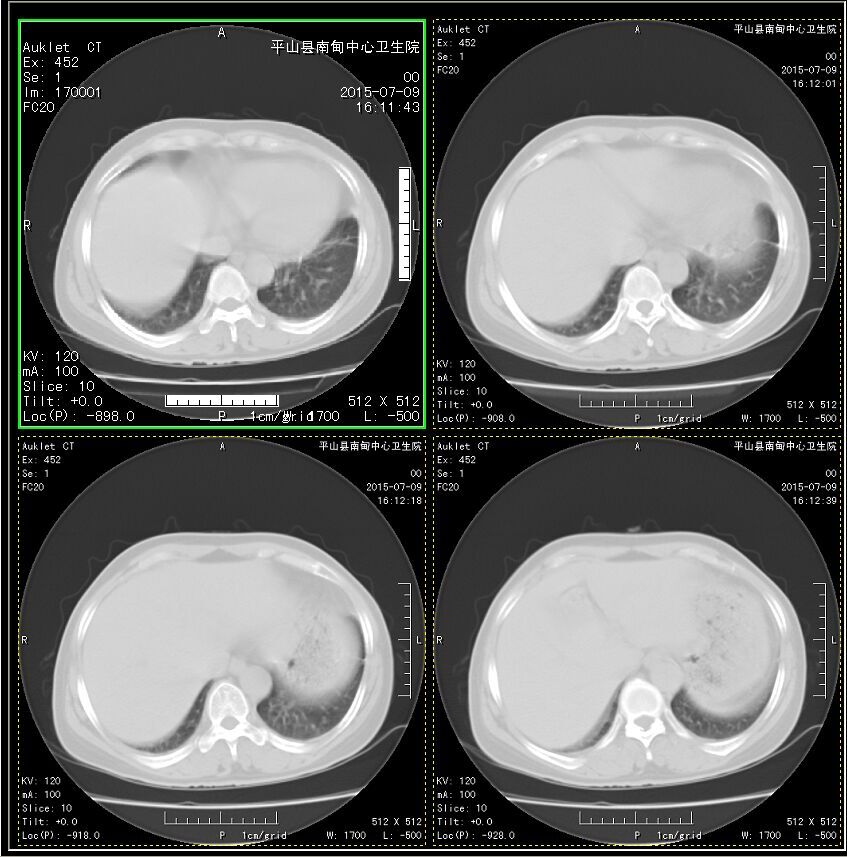

患者 女 50岁 左侧胸痛 10天

打个CT值吧,看密度好像是脂肪,脂肪疝?

源于胸壁,脓肿?

左心室壁瘤,请结合临床